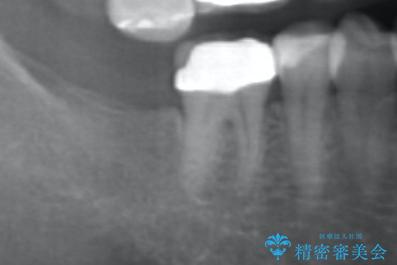

奥歯のインプラント治療

- 右下の奥歯を虫歯で喪失しそれ以来よく物が噛めず、改善を求めて来院されました。

入れ歯かインプラント治療のご提案を行い、よりしっかりとかめるインプラント治療を希望されました。

骨との結合する期間が早く、大きな咬合力にもしっかりと耐えることのできるストローマンインプラントを用いた咬合機能回復を計画します。

- 44万円(ストローマンインプラント・チタンカスタムアバットメント・仮歯・フルジルコニアクラウン)費用は治療当時の料金となります